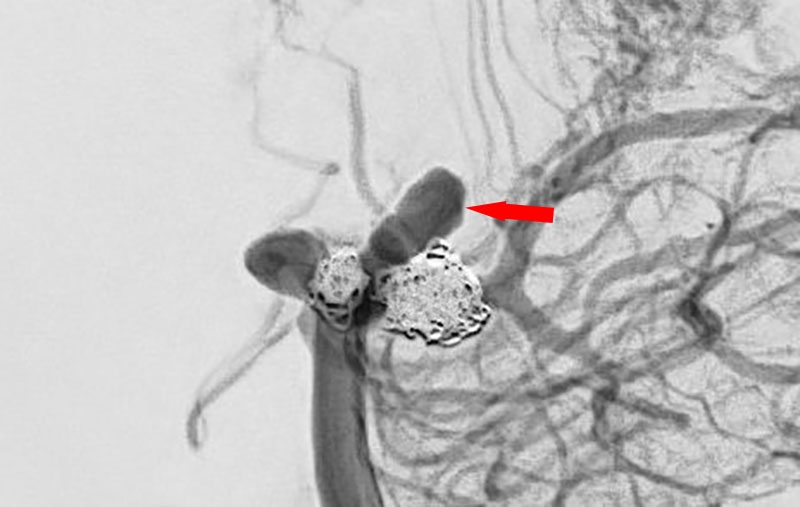

No.1630 手術前

No.1630 手術中

No.1630 手術後